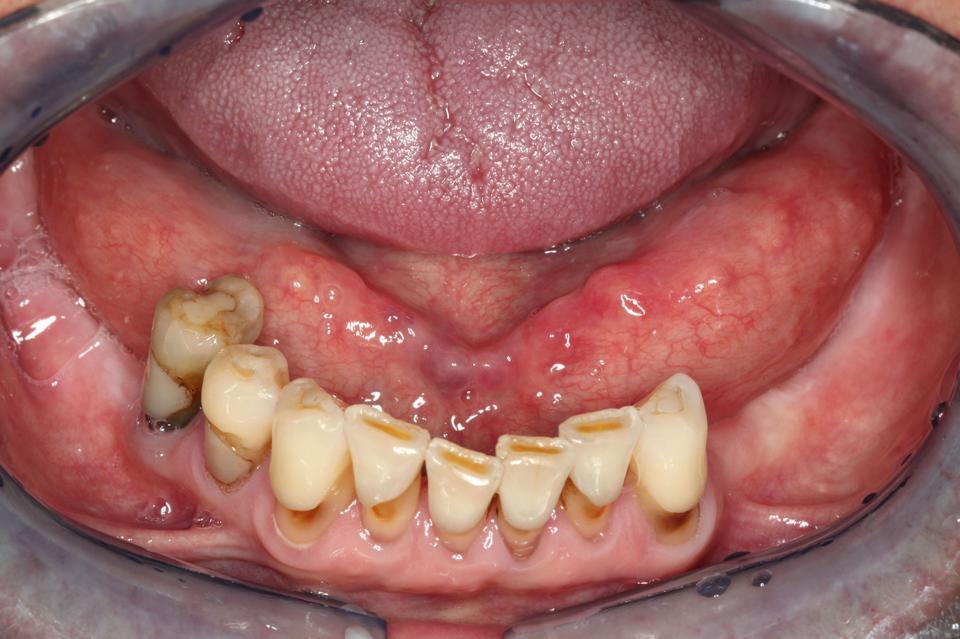

Zu Ihnen in die Praxis kommt eine 54-jährige Patientin und klagt über eine Schwellung unter der rechten Zungeseite. Gelegentlich treten in diesem Bereich Schmerzen auf. Manchmal verspürt sie Ähnliches auch auf der Gegenseite.